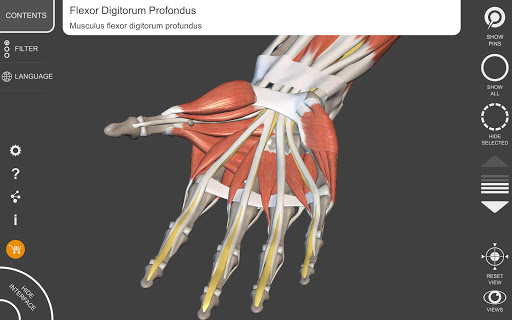

"Anatomy 3D Atlas" cho phép bạn nghiên cứu giải phẫu người theo cách dễ dàng và tương tác.

Thông qua giao diện đơn giản và trực quan, bạn có thể quan sát mọi cấu trúc giải phẫu từ mọi góc độ.

Các mô hình giải phẫu 3D đặc biệt chi tiết và có kết cấu lên đến độ phân giải 4k.

• Hệ thống cơ xương

• Xoay và phóng to từng mô hình trong không gian 3D

• Hình dung các cơ qua các lớp từ lớp nông đến lớp sâu nhất

• Bằng cách chọn một mô hình hoặc một ghim, thuật ngữ giải phẫu liên quan sẽ hiển thị

• Mô tả các cơ: nguồn gốc, chèn, chi phối thần kinh và hành động